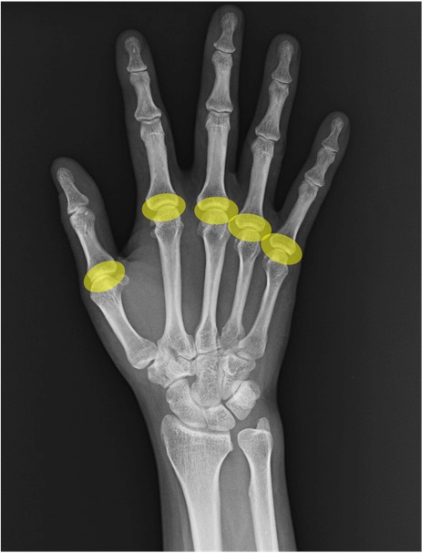

MP関節(metacarpophalangeal joint / MCP)

中手骨頭と基節骨底の関節。PA像で楕円形の関節裂隙と均等性、側面像で背側板(示唆)や脱臼の有無を評価。